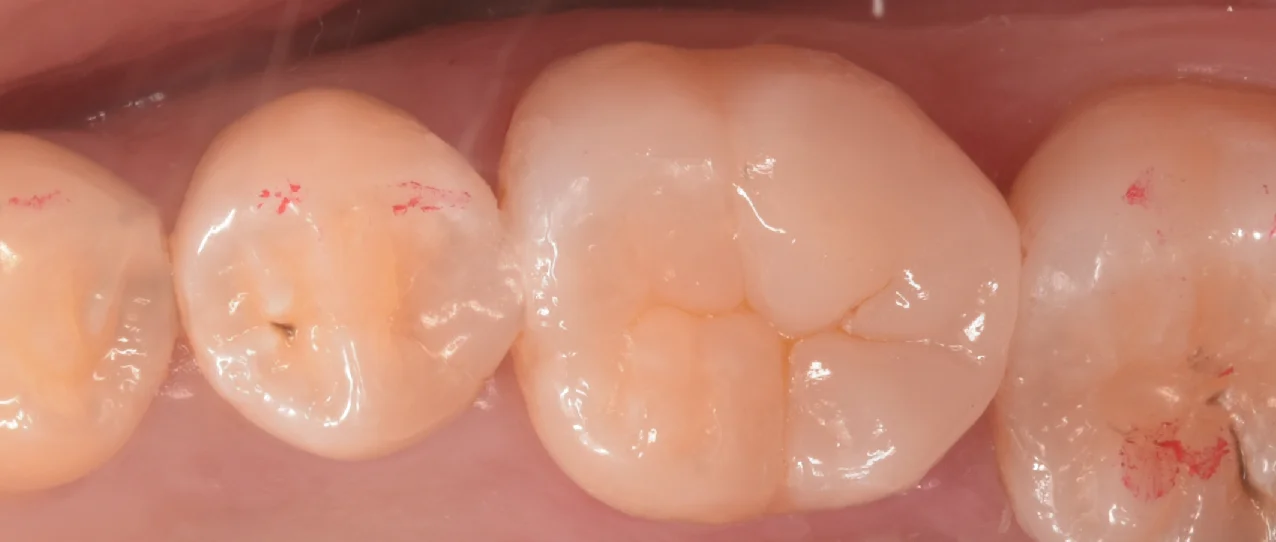

まずは術前からです。

歯科医師の方のCAD/CAMインレーを治療。|坂寄歯科医院(取手市藤代)

2〜3年ほど前に入れたCAD/CAMインレーと呼ばれるものが入っています。

ここの一部が欠けてしまい、虫歯になっているようです。

術前術後の写真がこちらです。

歯科医師の方のCAD/CAMインレーを治療。|坂寄歯科医院(取手市藤代) - 画像5